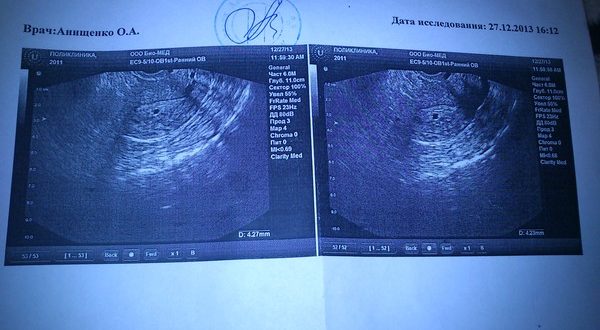

Узи матки и придатков

Как делают и подготовка к УЗИ матки и придатков – UZI.ONE Гинекологи часто назначают УЗИ матки и придатков. И то, как делают это обследование интересует многих пациенток. В…

Узи на 7 неделе беременности расшифровка

Узи на седьмой неделе беременности В последние десятилетия различные варианты УЗИ настолько прочно вошли в нашу жизнь, что ни врачи, ни пациенты не представляют себе медицину без ультразвука….